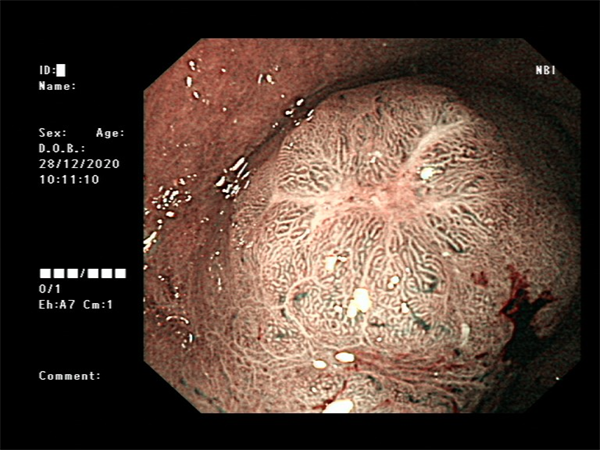

患者周某,男60岁,体检行肠镜发现直肠肿物,行肠镜下直肠黏膜下剥离术(ESD),术后病理:绒毛状管状腺瘤,局灶呈高级别上皮内瘤变。

· 放大胃肠镜精查

· 食管、胃、结直肠早期癌粘膜下剥离术(ESD)